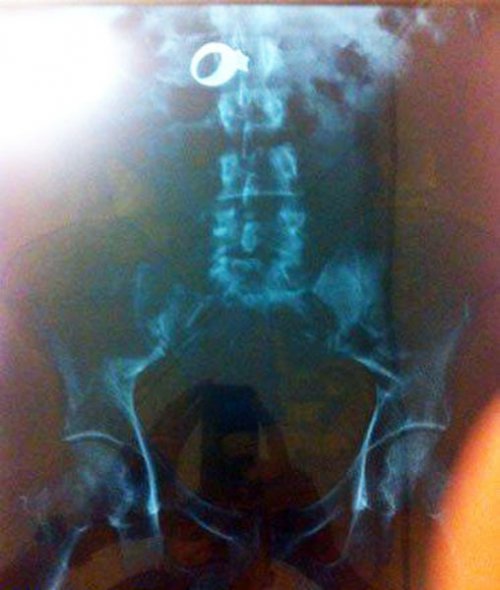

Не забываем и о классических снимках: кружка пива в заднем проходе!

Рентгеновский снимок кольца с бриллиантом внутри 30-летнего Уилфредо Гонзалез-Круз (Wilfredo Gonzalez-Cruz), из Чикаго. Мужчина украл кольцо из дома женщины в Сисеро (Cicero) и затем проглотил его.